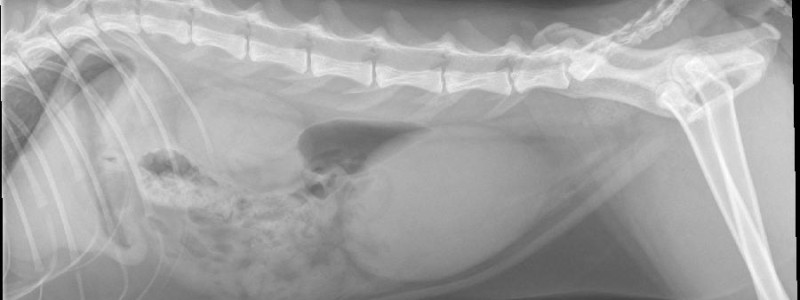

Een 'plaskater' is een kater die niet meer kan plassen doordat zijn urinebuis verstopt zit. Dit kan onder andere komen door steentjes, gruis of ontstekingmateriaal uit de urinewegen wat vastloopt in de plasbuis.

Dat klinkt misschien “gewoon vervelend”, maar het is écht een spoedgeval. Als een kat niet kan plassen, raakt de blaas overvol waardoor de nieren in verdrukking komen en de blaas zelfs kan knappen. Ook kunnen afvalstoffen die normaal via de urine worden afgevoerd zich in het lichaam ophopen, wat onder andere voor hartritmestoornissen kan zorgen. Het kan binnen korte tijd dus erg gevaarlijk worden.

We zorgen ervoor dat de verstopping wordt opgeheven (meestal met een katheter), legen en spoelen de blaas, starten medicatie en zo nodig een infuus, doen urine-onderzoek (en eventueel ander onderzoek) om de achterliggende oorzaak te achterhalen en houden de kat goed in de gaten in onze opname.